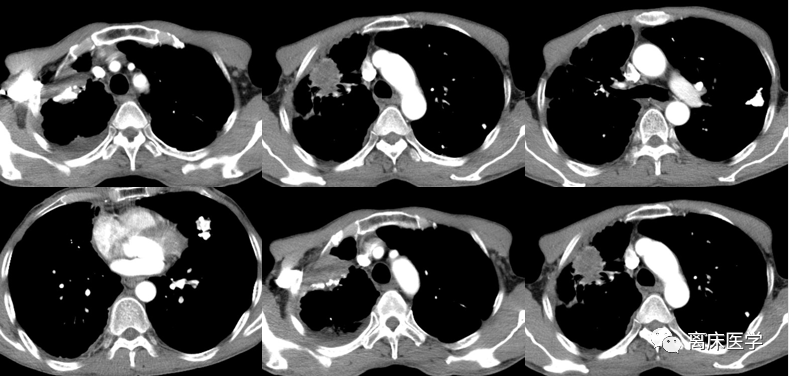

少见的胸腔积液病因之一,您能猜到吗?_mmhg_ml_病史

肺部阴影待查;2.胸腔积液.